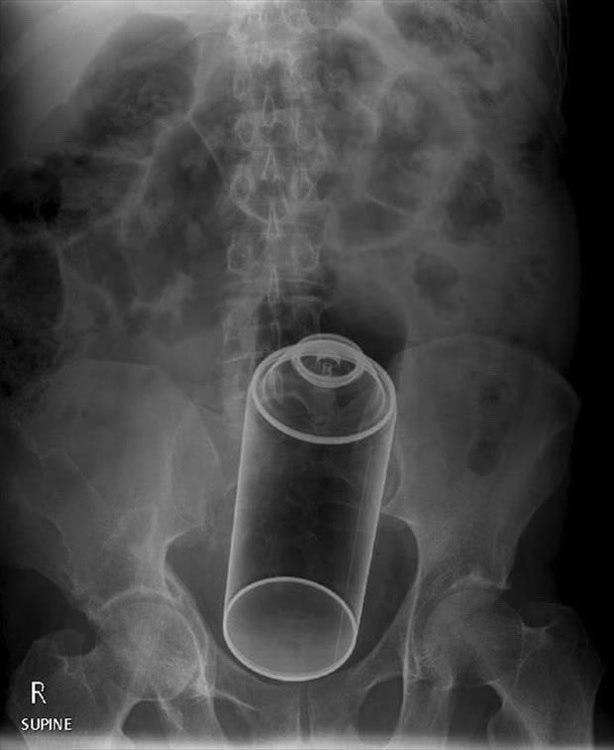

21-летний фрилансер из Ленобласти лишился прямой кишки и теперь будет жить с калоприёмником после неудачного эксперимента «для поднятия настроения».

Врачам дизайнер рассказал: заскучал, решил развлечься, засунул себе в очко дезодорант. Веселее не стало — попытался вытащить, не получилось. Оставил там. Проходил с баллоном в себе три дня, сильно заболело, вызвал скорую.

Прибывшие врачи госпитализировали его с необратимым некрозом тканей. Прямую кишку пришлось ампутировать и теперь сверхразум будет жить с калоприёмником.